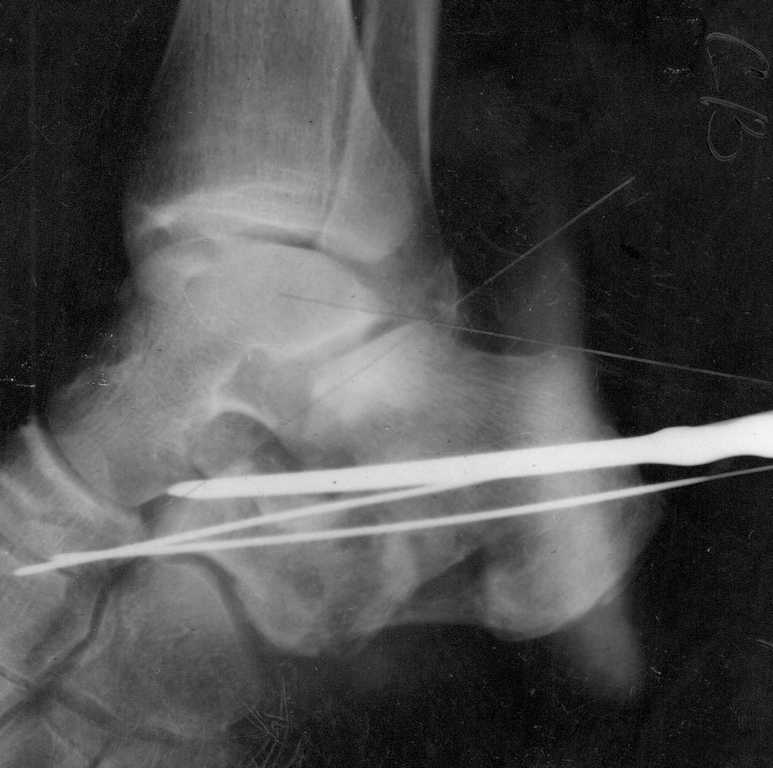

Перелом типа "утиного клюва" как и указано ранее,наименее инвазивно - ввести винт Шанца в основной фрагмент, под ЭОП контролем репонировать к суставной тарана с восстановлением формы пятки и всех углов и фиксировать - можно спицы, можно винты канблированные. Если же сроки более нескольких дней - то придется видимо открываться.

Сделали данному больному операцию. Фиксация перелома спицами. Это интраоперационный снимок.